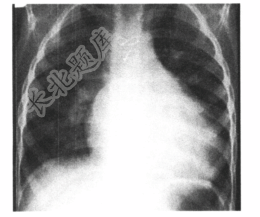

- [材料题] 患儿,女。出生后4个月开始出现发绀,气促。查体:听诊胸骨左侧缘2~3肋间隙闻及收缩期杂音,肺动脉瓣第二心音消失。X线胸片如下图所示。

- 多项选择题1.最可能的诊断是( )

C、法洛四联症